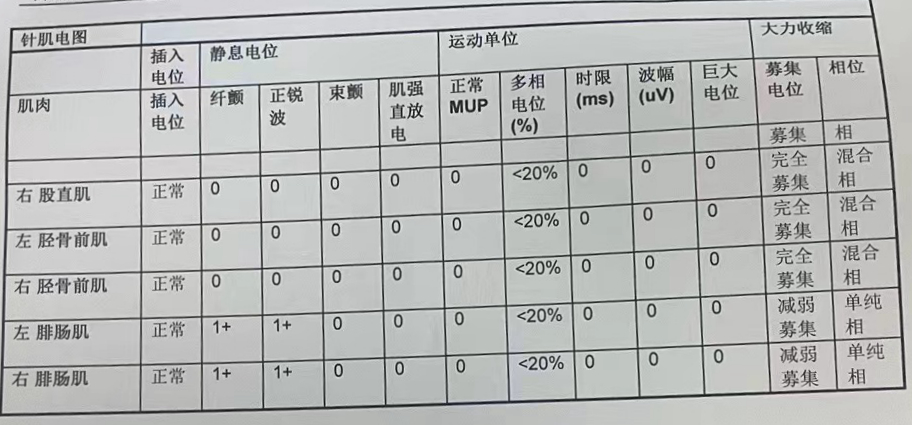

脊柱手术中的肌电监测可以实时监控支配肌肉活动的颅神经、脊髓神经根丝以及外周神经的功能,有效减少术中意外发生的风险,为手术保驾护航。

患者肌电图报告